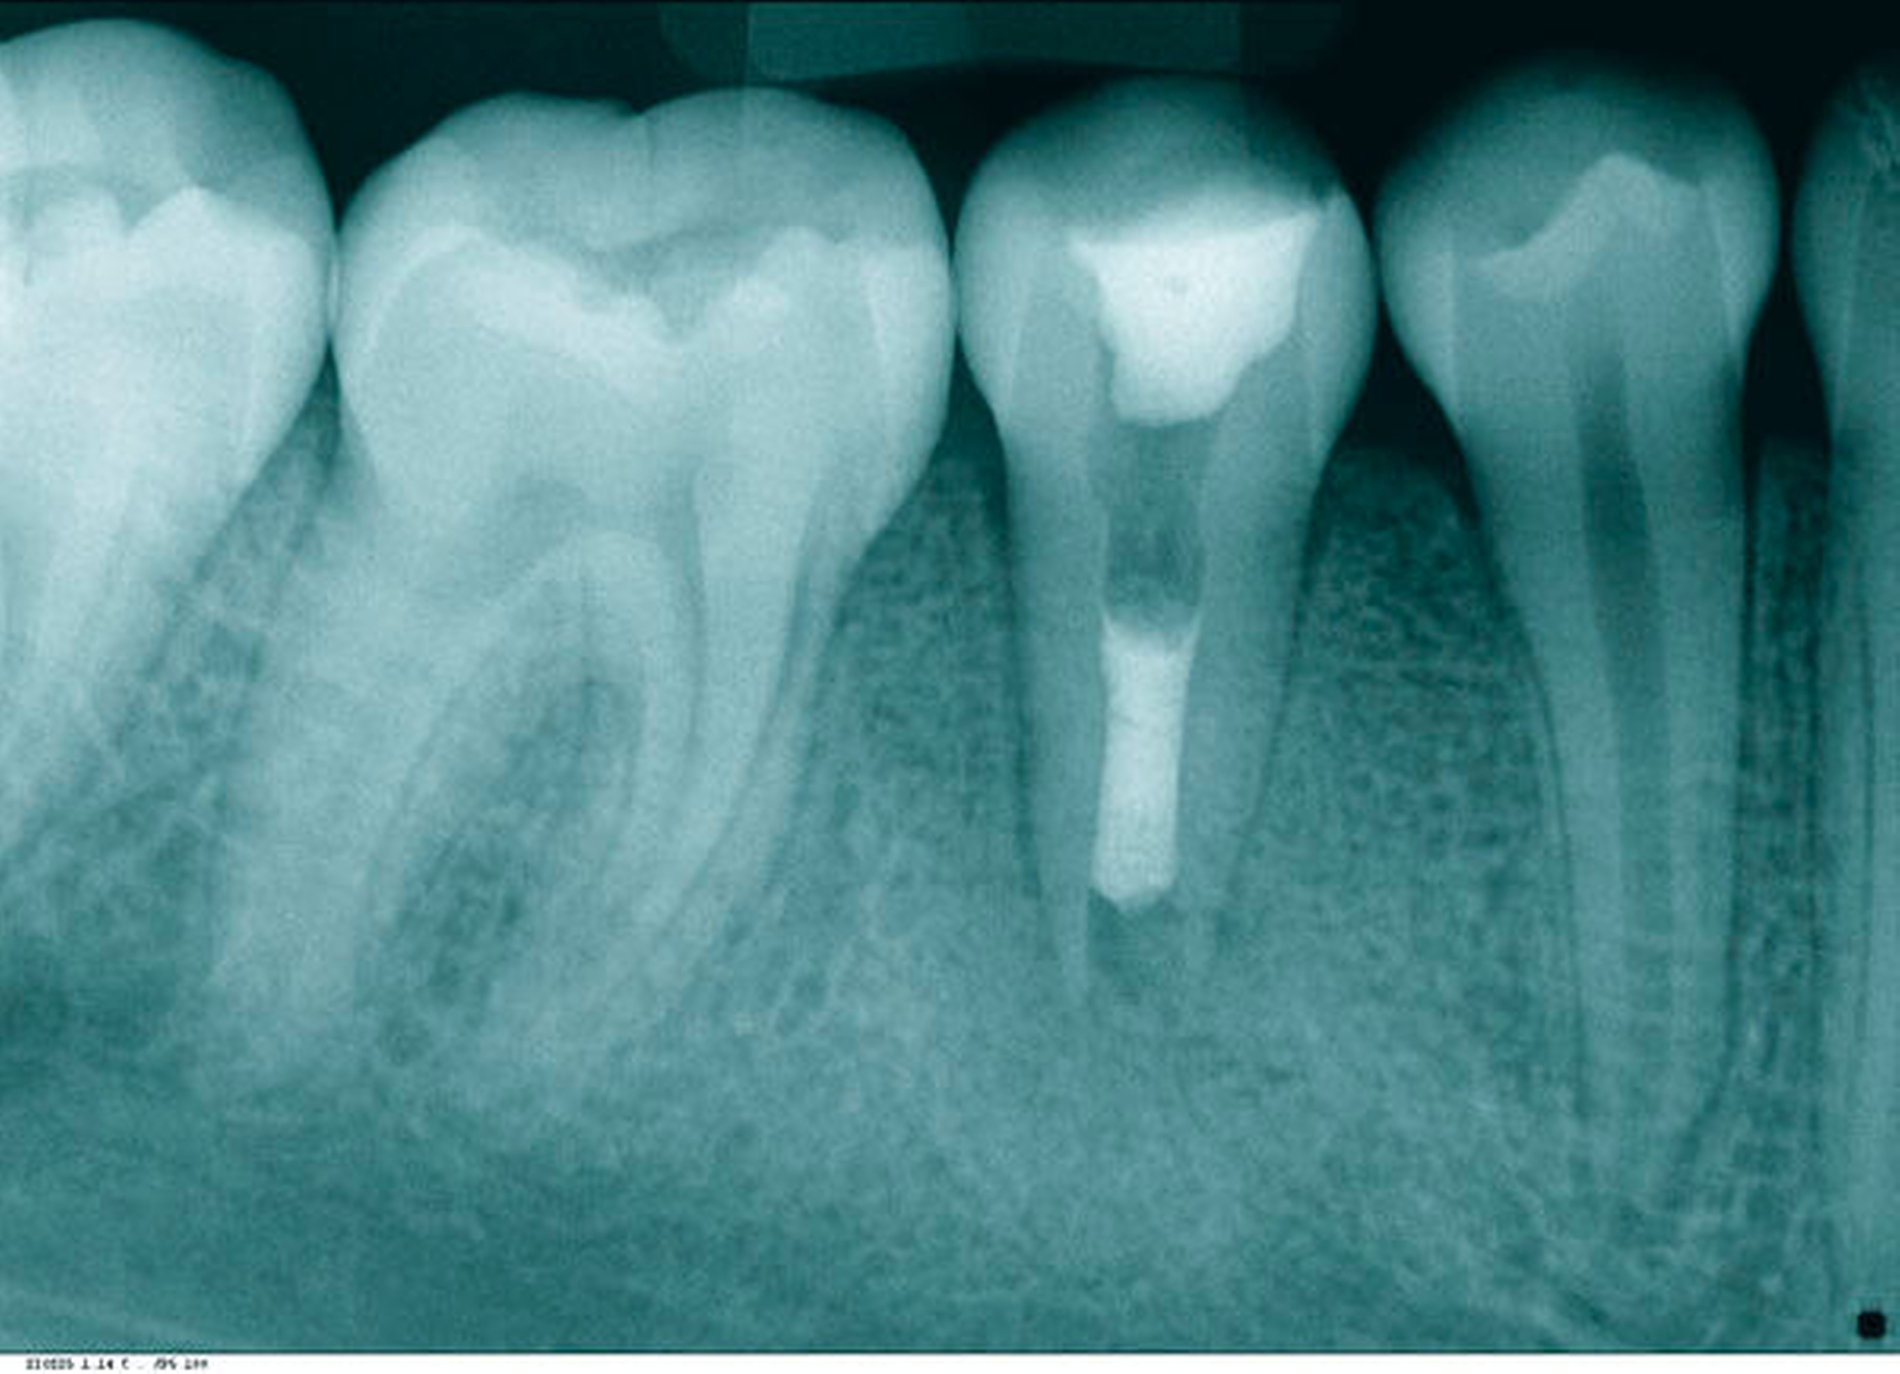

Die zweite Therapiesitzung folgte eine Woche später. Der Fistelgang war bereits ausgeheilt. Nach Spülung mit NaOCl 5 % und EDTA 17 % sowie der Schallaktivierung mittels EDDY (VDW, München) erfolgte die Trocknung des Zahnes. Im Anschluss wurde ein apikaler Verschluss mit weißem ProRoot MTA (Dentsply Sirona, York, PA, USA) appliziert (Abbildung 7). Der Plug wurde auf eine Länge von 15 mm eingebracht – genau der Punkt, ab dem die Patienten das Sondieren wieder gespürt hat. Zur Kontrolle des Plugs erfolgte eine Kontrollaufnahme vor definitivem Verschluss (Abbildung 8).